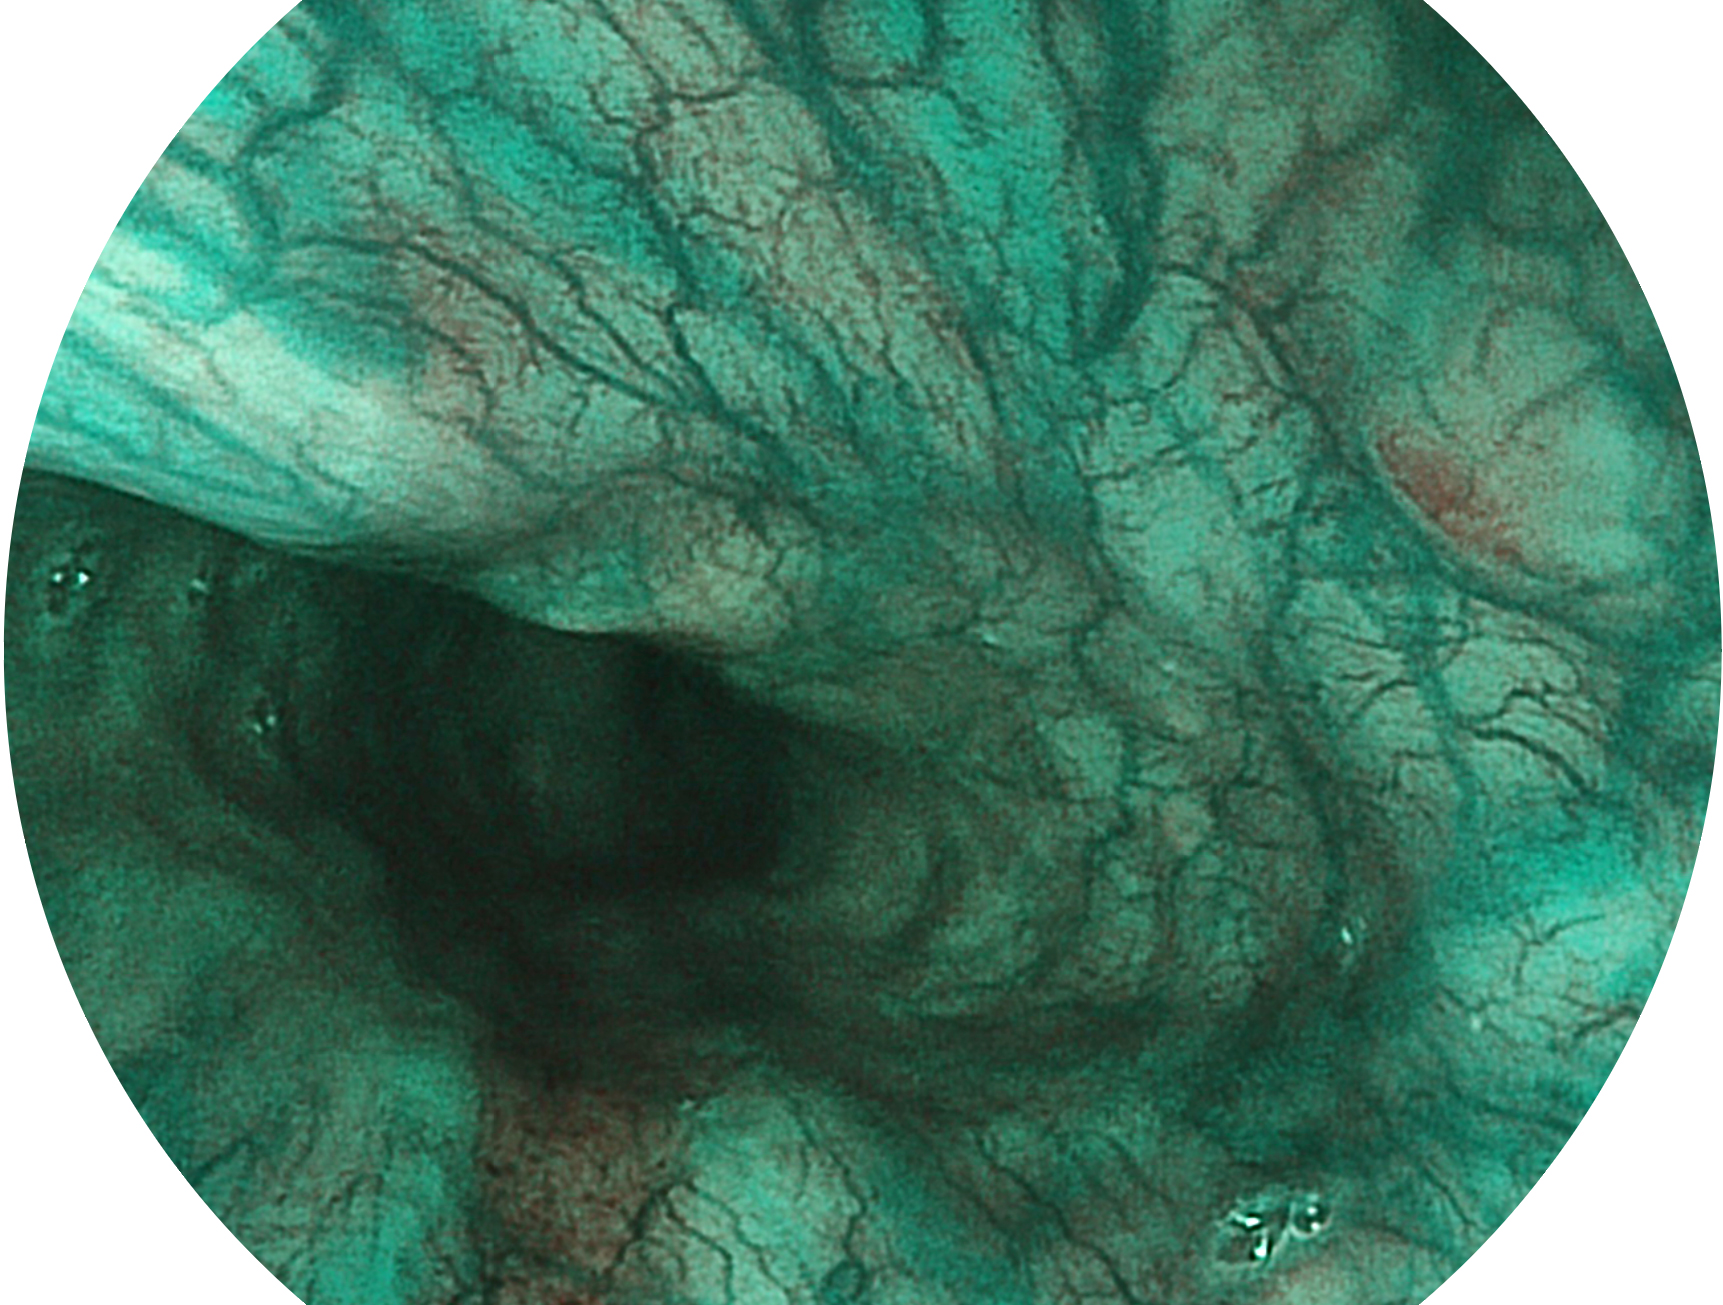

美狮贵宾会官网新开发的内镜染色技术,主要是基于多波长LED 光源的开发,VLS-55Q 四波长LED 光源是由四个不同颜色的LED光按照相应照明模式所规定的特定发光比例进行合束后形成,合束后形成的照明光的光谱由红光、绿光、蓝光及蓝紫光这四个不同的波段范围构成。具有更高光谱自由度,通过光谱比例的控制,实现了聚谱成像技术,英文全称为“Spectral Focused Imaging, SFI”,缩写为“SFI”和光电复合染色成像技术,英文全称为“Versatile Intelligent Staining Technology, VIST”,缩写为“VIST”。